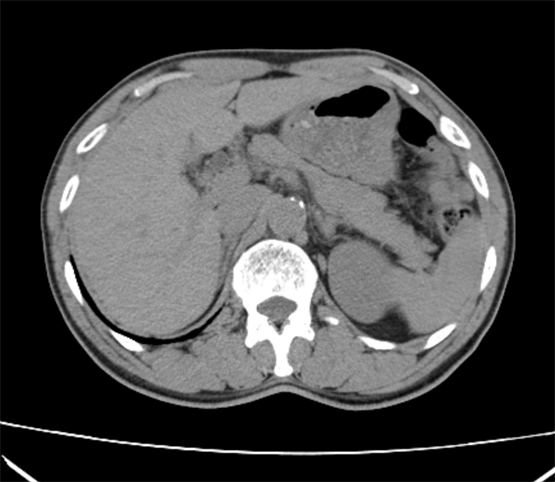

1.常规平扫加增强:宽腾医疗CT系列具有智能追踪和经验值等多种增强扫描方案,定制化血管增强和多期脏器增强扫描解决方案,采用最快0.5秒机架旋转,1.75大螺距扫描,最低70kv低剂量智能毫安调节技术,实现低剂量/低辐射/低对比剂/低速率“四低”临床检查方案,满足临床诊断。

目前,通过对当地其他医院的CT和现已装机的64排128层螺旋CT图像质量进行对比分析发现,两者在扫描范围上有很大差异,这对于提高临床医生对疾病的认识和诊治水平有着十分重要的意义;另外,其相对于普通设备而言具有更大的体量优势和功能优势,使得它能够满足不同病人的需求。同时,对心脏成像、脑血管综合解决方案、血管成像、肺结节检查及结肠病变普查等多项科研技术实现了重大突破。